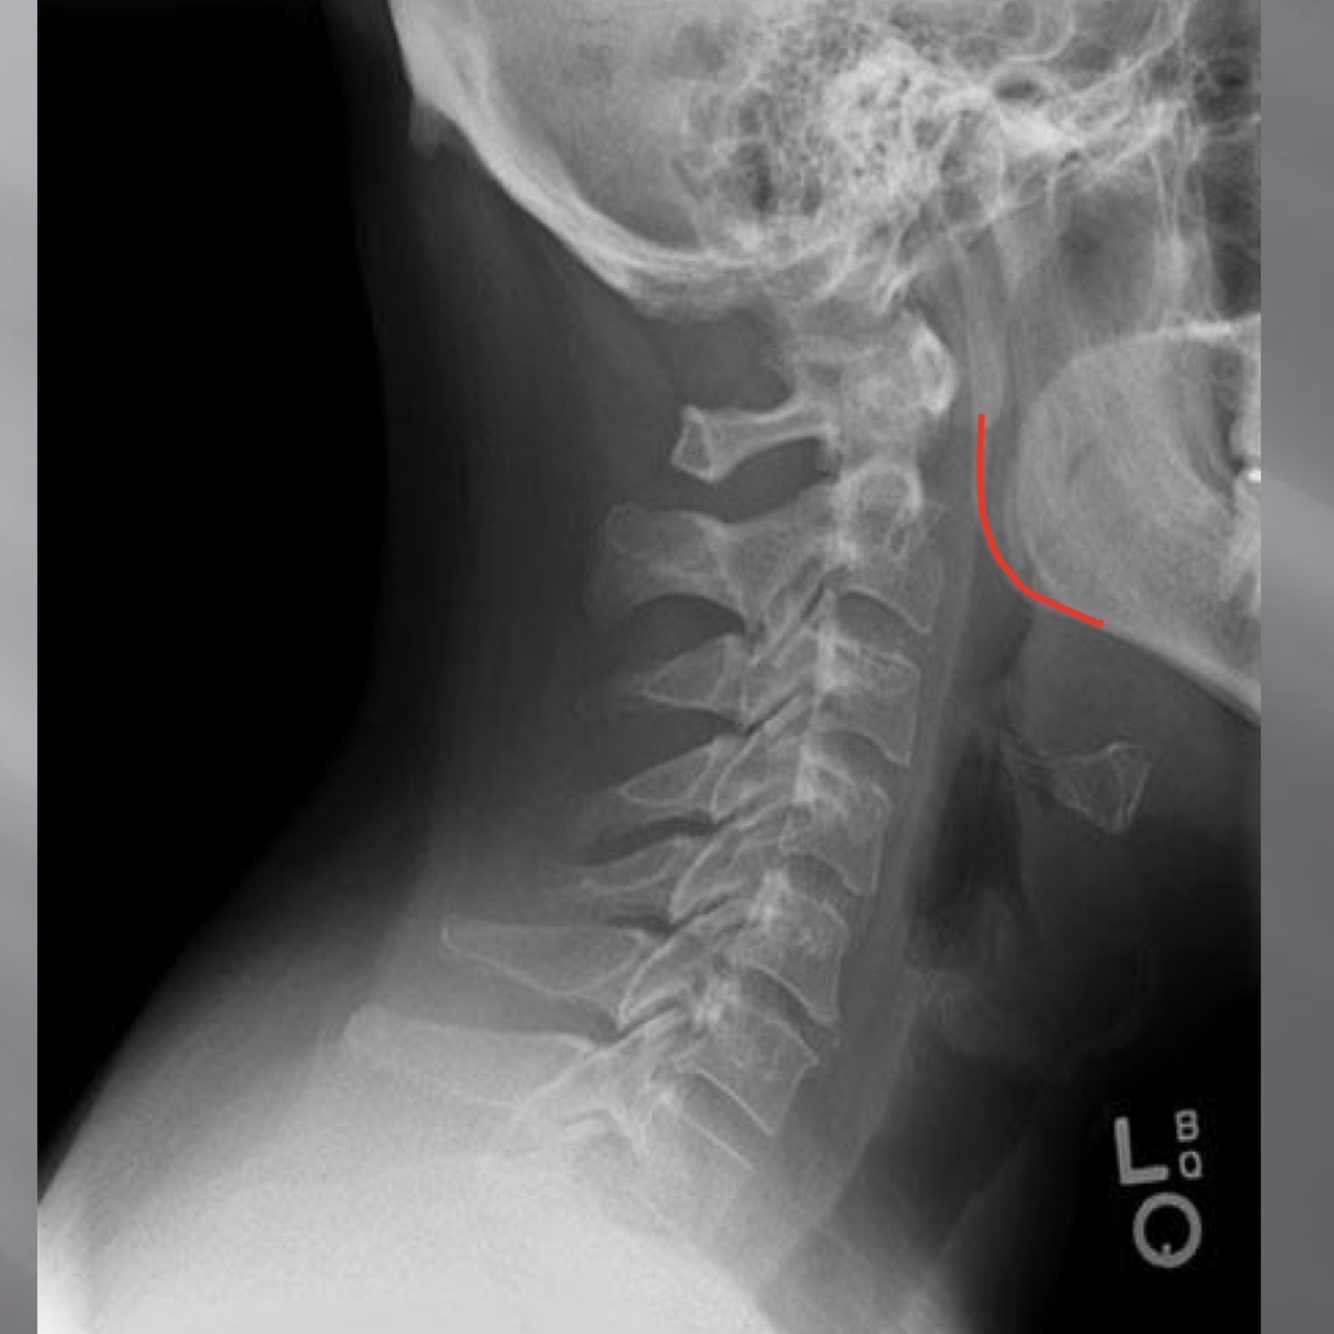

LATERAL CERVICAL LANDMARKS lateral cervical view

posterior arch of C1

vertebral body c2-c7

anterior tubercle c1

zygapophyseal joints

occipital condyle

superior endplate tips

inferior endplate tips

Lateral cervical view

disc spaces

atlanto-dental interspace

hyoid bone